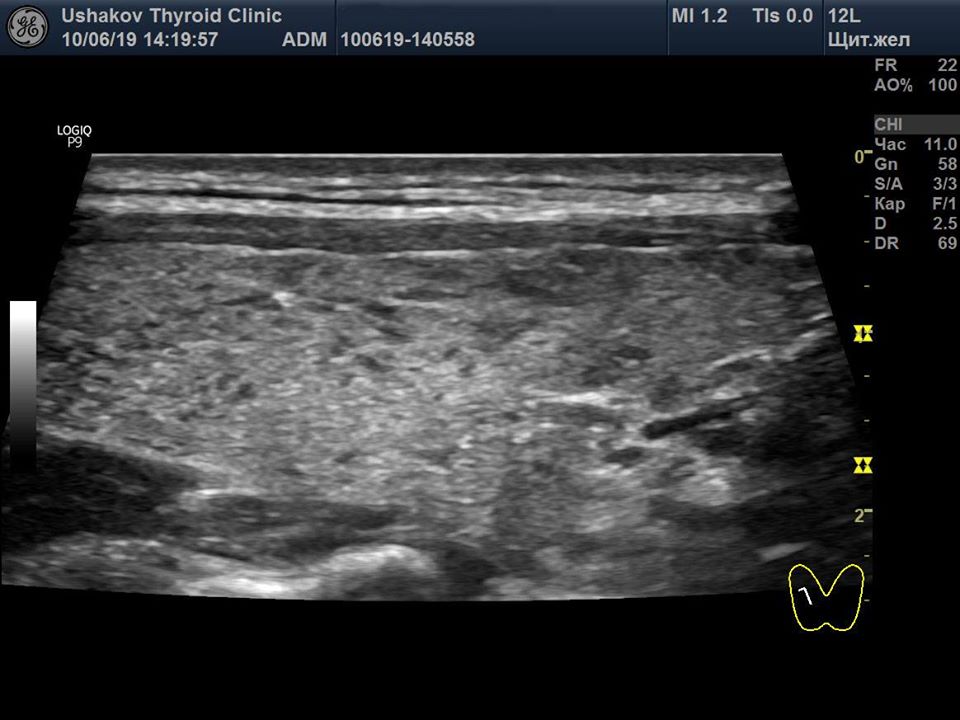

Пример такого восстановления щитовидной железы при аутоиммунном тиреоидите представлен на

рис. 4. Этот пример показывает, как за счёт регенерации в ЩЖ пациентки через 10 месяцев значительно уменьшилось количество долек с признаками деструкции и замещения лимфоидной тканью (округлых гипоэхогенных участков), являющихся признаком тиреоидита Хашимото. Вместо лимфоидной ткани появилась полноценная гормонообразующая ткань ЩЖ. Одновременно с репаративным восстановлением структуры ЩЖ значительно уменьшилась активность иммунной помощи железе, что заметно по уменьшению в крови титра антител к ТПО и ТГ.

Рисунок 4 (начало) Правая доля щитовидной железы у пациентки 35 лет (продольная проекция). Слева – состояние доли 13.08.18 (АТ-ТПО 775 МЕ/л [<5,6], АТ-ТГ 30 МЕ/л [<4,1]), справа – 10.06.19 (АТ-ТПО 195 МЕ/л [<5,6], АТ-ТГ 9,5 МЕ/л [<4,1]). Гормональные медикаменты никогда не использовала.

|

Рисунок 4 (окончание) За 10 месяцев произошло значительное улучшение структуры ЩЖ. В ткани щитовидной железы значительно уменьшилось количество лимфоидной ткани в дольковых сегментах, осталось очень малое количество мелких долек с признаками деструкции и лимфоидного замещения.